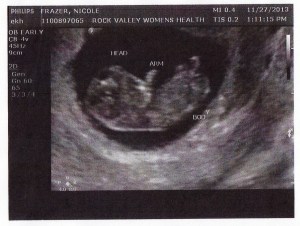

In the beginning, when we found out my daughter and her husband were expecting, BB was just “text speak” for baby.

As in, they’re having a BB, squeeeeee!

Then we found out it was a boy and BB meant Baby Boy.